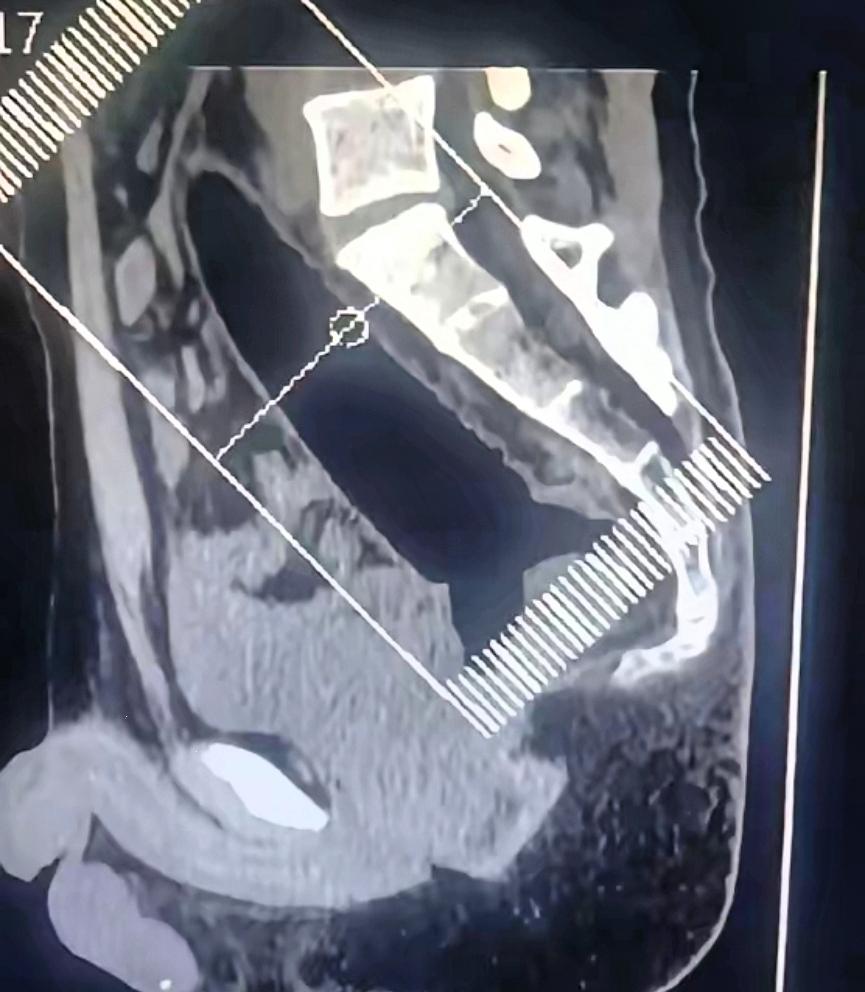

“悲剧还是发生了!”一男子捂着屁股去医院求助,说屁股卡了个东西,然而,当医生询问卡住的东西为何物时,男子支支吾吾不肯说实话,之后医生才发现这哪是卡了东西,分明就是一根异物深入了直肠,最后手术取出一根22厘米的透明异物! 这哪是小麻烦,分明是拿命开玩笑!医生折腾一小时才把这玩意儿取出来,动用全身麻醉、全套手术器械,这些本应用在正经急救上的资源,全给这哥们儿的一时冲动买单了。 醒来后他编瞎话说是干活摔伤,那尴尬劲儿隔着纱布都能看出来。真别觉得身体是自己的就能瞎折腾,那些你以为的“隐秘刺激”,代价可能是手术台、医疗费,还有一辈子的心理阴影。健康从来不是可以透支的信用卡,有些身体的底线,一旦碰了,哭都来不及!